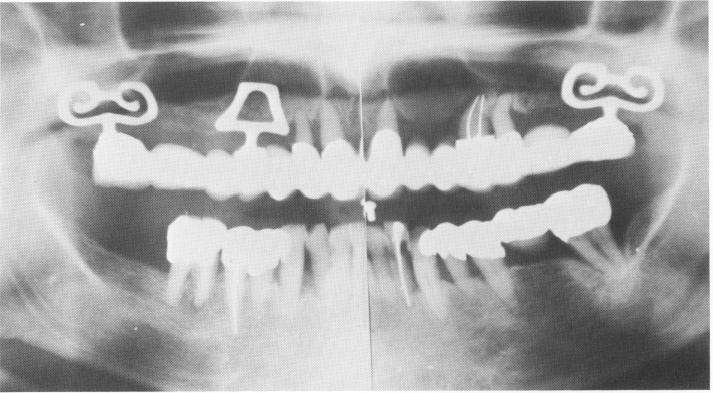

Fig. 11-84. A Panorex of the completed upper restoration. This was a referred patient who requested that only the upper arch be reconstructed. Today, since we know the true value of the blades, the anterior teeth would be extracted and replaced by two more blade implants.

1 Panorex of completed maxillary restoration over bladevents